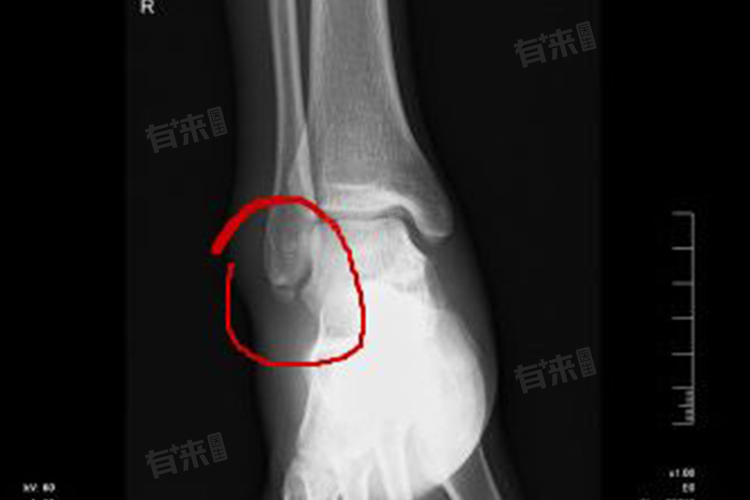

1、受伤部位:不同部位骨裂恢复时间不同,血运丰富的部位,如肋骨、锁骨,恢复相对较快,一般1-2个月。因丰富血液能为骨裂愈合提供充足营养和氧气。而血运较差的部位,如腕舟骨、距骨,恢复时间较长,可能需3-6个月,因营养物质供应相对不足,影响愈合速度。

3、骨裂严重程度:轻微骨裂,裂纹细小,对骨骼整体结构影响小,恢复快,1-2个月可愈合。若骨裂范围较大,甚至伴有轻度移位,恢复时间延长,可能需3个月左右。因较大骨裂需要更多时间修复受损骨质,重建骨骼结构。